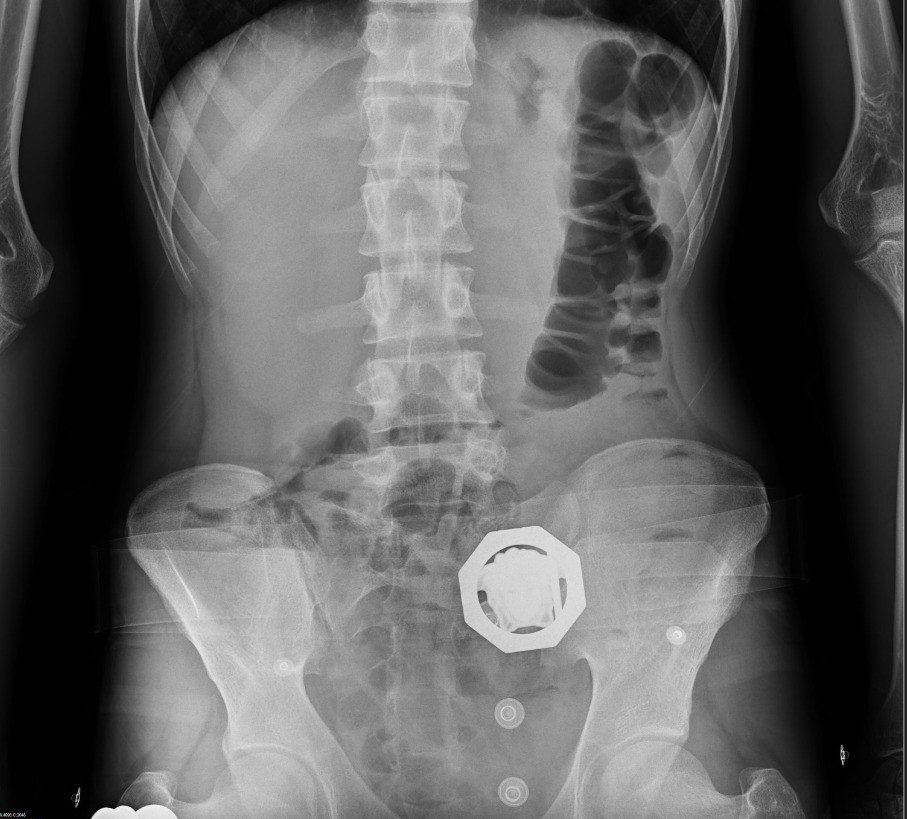

Diyarbakır’da 4 kişinin sindirim sisteminden 840 gram eroin ele geçirildi: 4 kişi tutuklandı

Diyarbakır'da şüpheli 4 kişinin sindirim sisteminden 121 parça halinde 840 gram eroin ele geçirildi.

Diyarbakır'da şüpheli 4 kişinin sindirim sisteminden 121 parça halinde 840 gram eroin ele geçirildi. Gözaltına alınan şüpheliler tutuklandı.

Araçta bulunan 4 şahsın ilk etapta yapılan kaba üst aramalarında herhangi bir suç unsuruna rastlanılmadı. Şahısların tedirgin haller sergilemesi ve rahatsızlık belirtisi vermeleri üzerine, adli makamlardan alınan karara istinaden yapılan tıbbi kontrollerde şüphelilerin vücut boşluğu/sindirim sisteminde 121 parça halinde 840 gram eroin ele geçirildi.